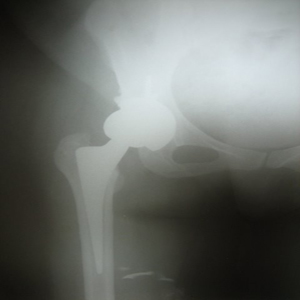

coimbatore-orthopaedic-joint-replacement-maternity-child-welfare-centre-india Uncemented Hip Replacement

NEW TECHNIQUE FOR HIP ARTHRITIS

30 years old lady presented with complaint of pain right hip since 7 yrs and getting worse since 1 month. She is unable to walk and stand for a long time.

On examination she is having a painful limp, shortening of right lower limb, her hip movements are restricted and painful.

Xray showed evidence of old perthes disease and secondary osteoarthritis of right hip.

Hip Arthritis

In view of her young age , an uncemented Total Hip Replacement was carried out.

Hip Arthritis Uncemented Replacement

Post operative period was uneventful and she is walking painfree from 2nd post operative day .